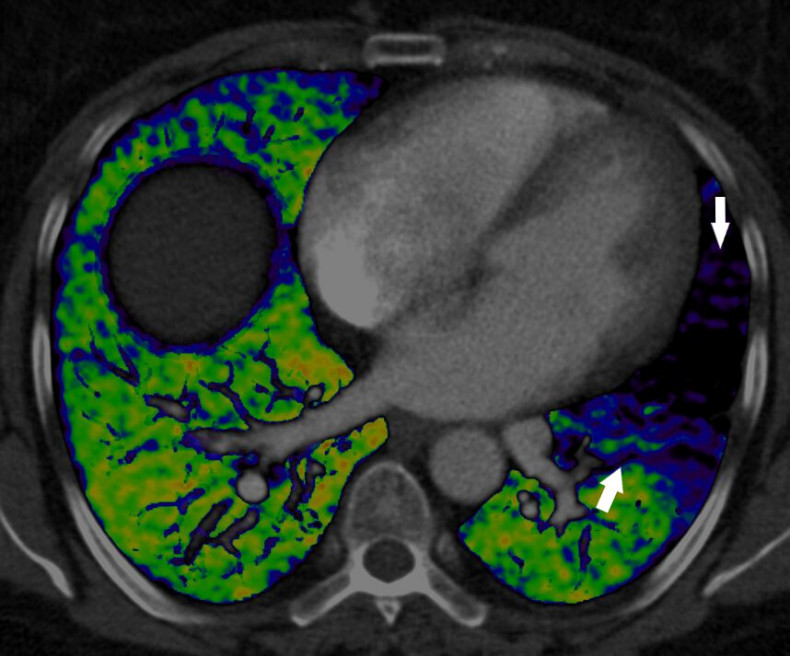

Dual energy CT is an emerging technology that combines two X-ray beams to predict the function of the lung’s blood vessels. This image demonstrates the effect of a blood clot in the left lung which is preventing blood from reaching the lungs (arrows) and as a result, preventing the oxygenation of blood in this part of the lung. The normal lung is well supplied by blood vessels (shown in green).